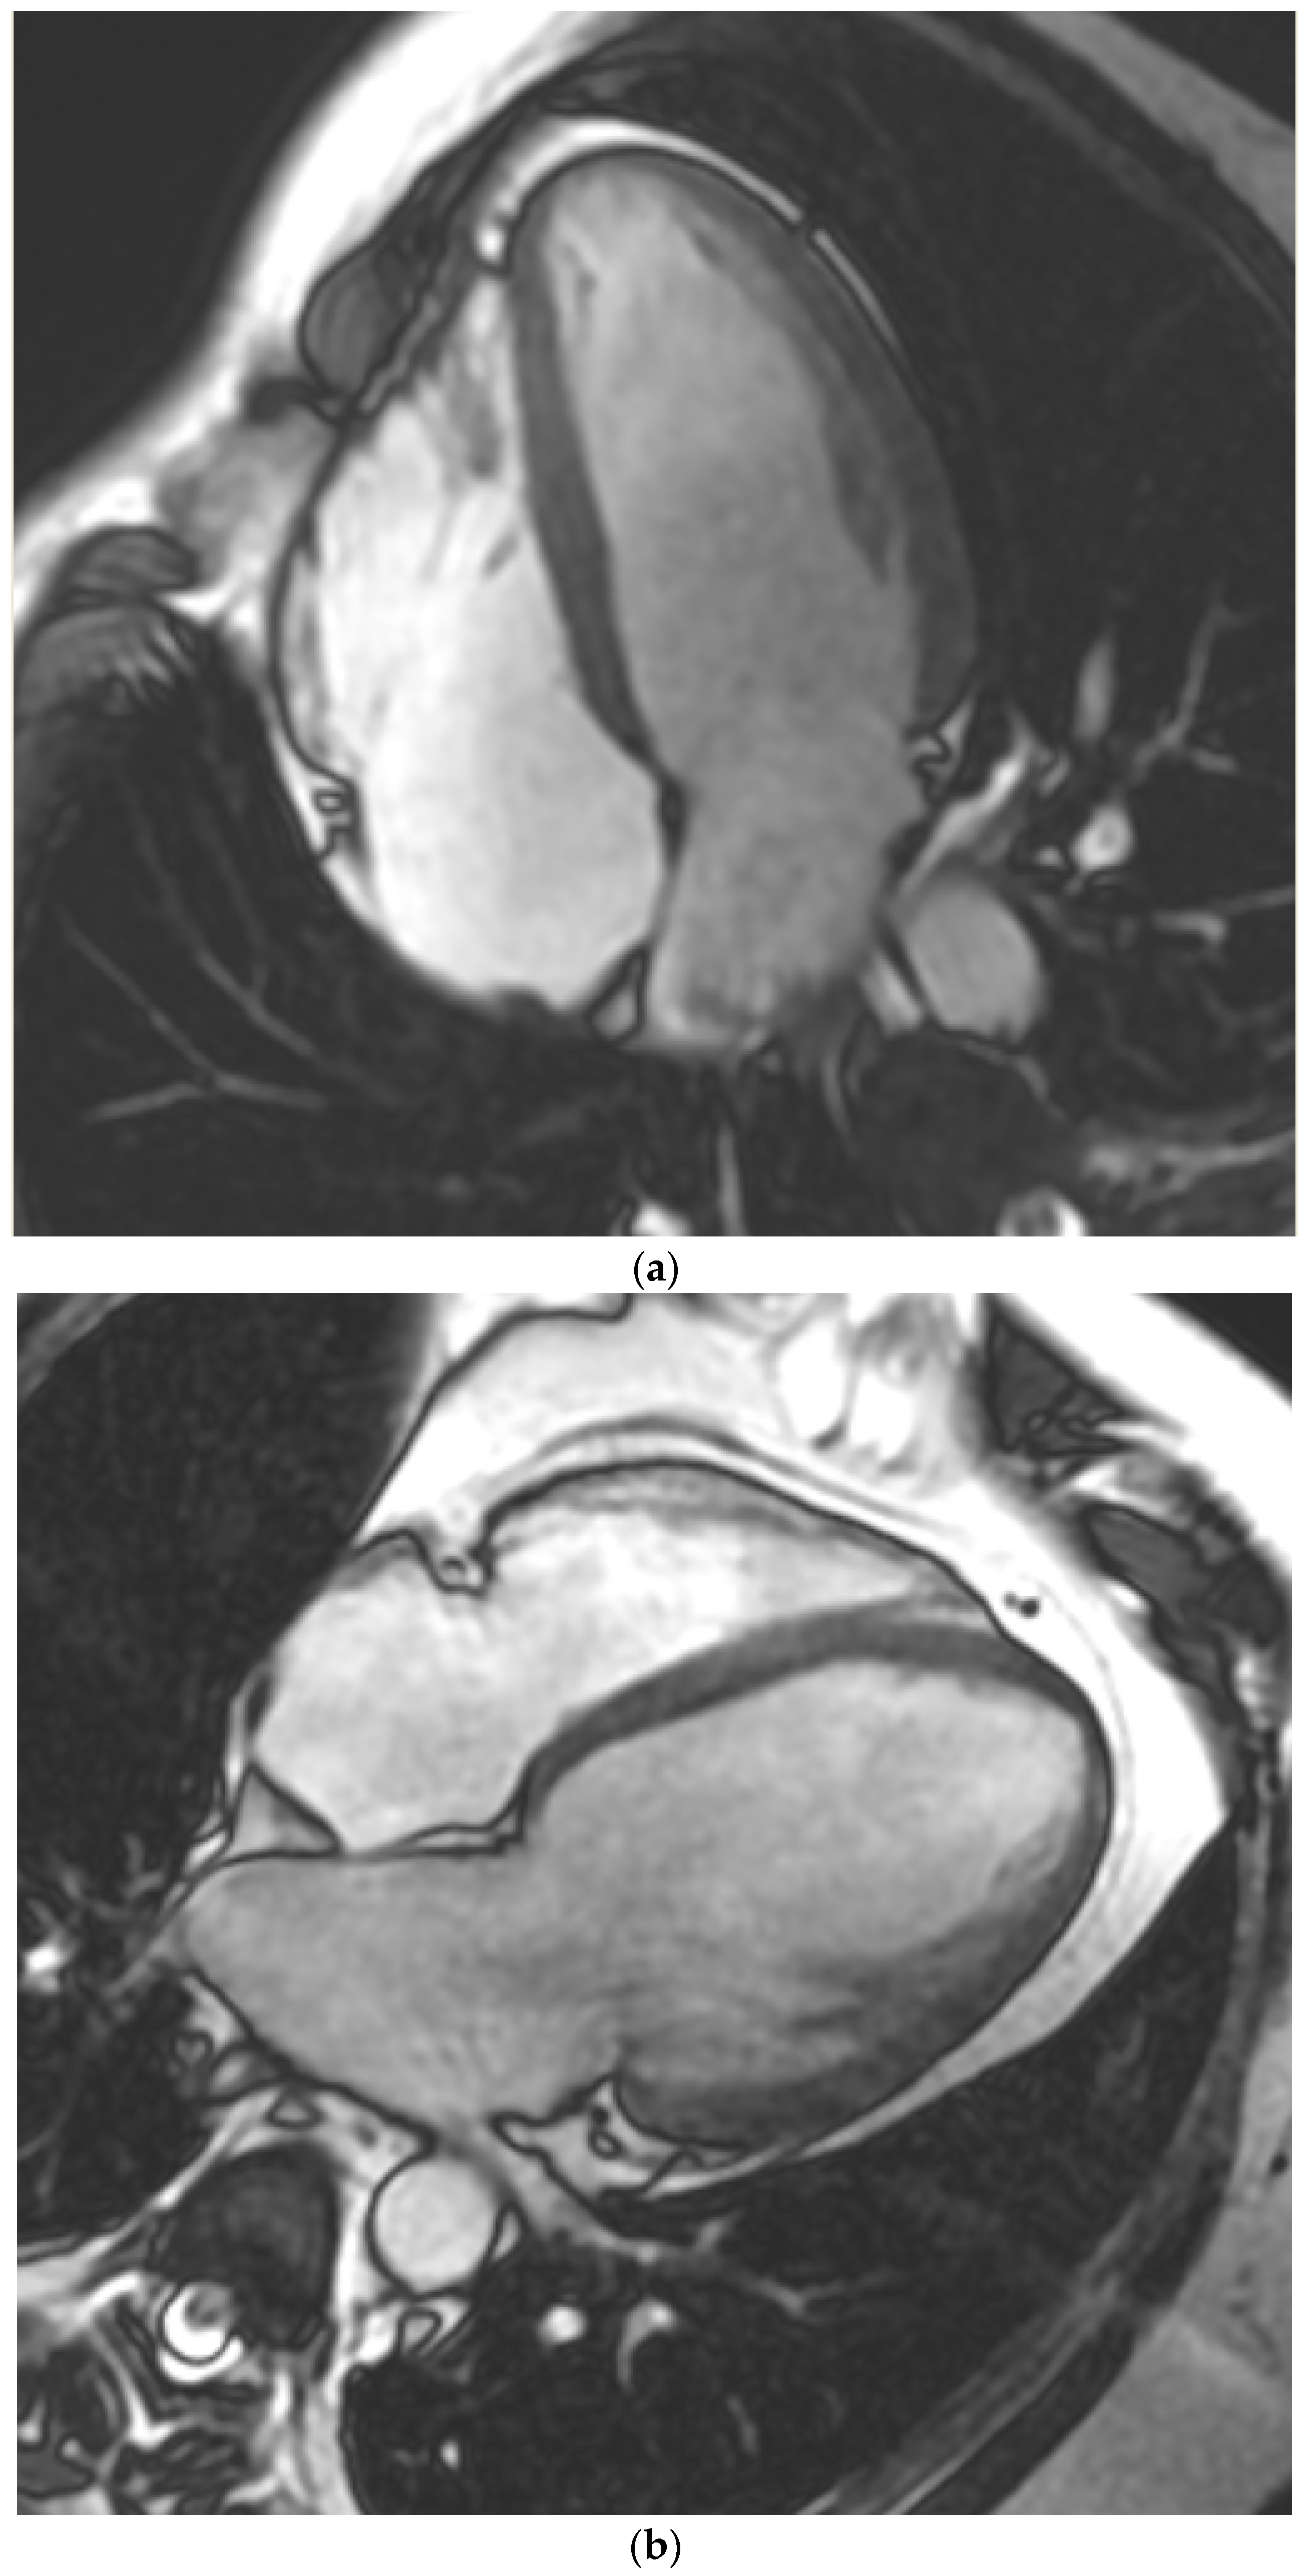

2.2. Cardiovascular Magnetic Resonance